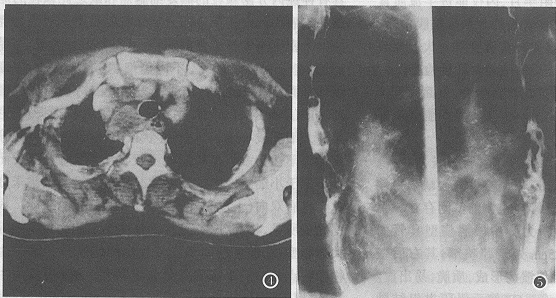

例3,男,63岁,胸痛半年,声嘶月余,外院MRI示中纵隔多发实质性肿块,以纵隔淋巴瘤转入我院。B超示肝左叶转移瘤。食管吞钡:气管分叉平面向下食管长约6.0cm粘膜中断破坏,壁僵硬,伴不规则充盈缺损。X线诊断为胸中段髓质型食管癌(图5)。锁骨上淋巴结活检:转移性小细胞未分化癌。CT及胸片示两肺转移瘤及纵隔淋巴结转移。

图4 右上纵隔气管旁淋巴结肿大,脂肪间隙清楚。